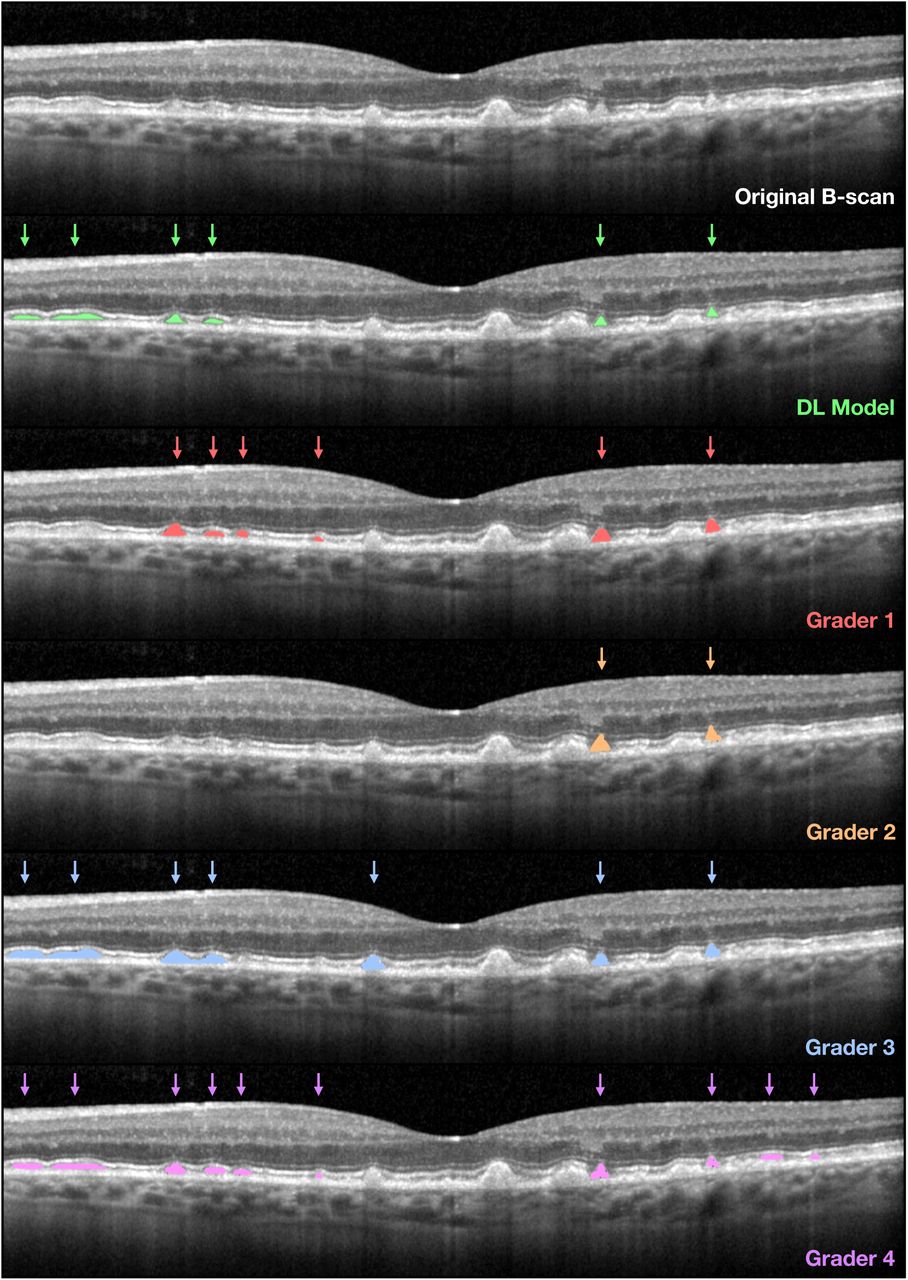

This model detects and segments Reticular Pseudodrusen (RPD) instances in Optical Coherence Tomography (OCT) B-scans. The instance segmentation model used a Mask-RCNN [1] head with the ResNeXt-101-32x8d-FPN [2] backbone (pretrained on ImageNet) implemented via the Detectron2 framework [3]. The model produces outputs that consist of bounding boxes and segmentation masks that delineate the coordinates and pixels of each instance detected, which are assigned a corresponding output probability. A tuneable probability threshold can then be applied to finalise the binary detection of an RPD instance.

The model was trained using the prospectively-collected, baseline OCT scans (prior to any treatments) of individuals enrolled in the LEAD study [4] imaged using Heidelberg Spectralis HRA+OCT. OCT B-scans from 200 eyes from 100 individuals in the LEAD study were randomly selected to undergo manual annotations of RPD by a single grader (HK) at the pixel level, following training from two senior investigators (RHG and ZW). Only definite RPD lesions, defined as subretinal hyperreflective accumulations that altered the contour of, or broke through, the overlying photoreceptor ellipsoid zone on the OCT B-scans were annotated.